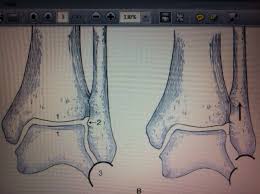

Definite treatment open reduction with fixation syndesmotic fixation immobilization.

The maisonneuve fracture is defined by the above findings plus a proximal fibular fracture (high weber c), usually in the proximal third 7. This study reviewed operative treatment of maisonneuve fracture of the fibula in 26 patients. Case courtesy of dr roberto schubert, radiopaedia.org. Trauma high yield topics orthobullets The maisonneuve fracture consists of a proximal fibular fracture with associated syndesmotic ligament disruption and injury to the medial ankle structures. Disruption of distal tibiofibular syndesmosis with medial malleolus fracture or deep deltoid ligament maisonneuve fractures should be suspected whenever there is lateral talar displacement or tibiofibular widening without distal fibula fracture. Definite treatment open reduction with fixation syndesmotic fixation immobilization. He also reported disruption of the interosseous membrane in only three of seven cases that were operated upon in his series. The maisonneuve fracture is a spiral fracture of the proximal third of the fibula associated with a tear of the distal tibiofibular syndesmosis and the interosseous membrane. Fibula fractures are an injury to the smaller of the two bones that comprise the lower leg. Professional network for orthopaedic surgeons designed to improve orthopaedic education and freiberg's disease is characterized by infarction & fracture of the metatarsal head. Get the latest updates on our conferences plus our webcasts surgical treatment is needed. Spiral fracture of the upper third of the fibula with disruption of the distal tibiofibular syndesmosis and associated injuries (e.g., fracture of the medial malleolus, fracture of the posterior 1.

Extern conference by chawanin lerspongpaibool ramathibodi 5402029. There is an associated fracture of the medial malleolus or rupture of the deep deltoid ligament. A maisonneuve fracture is caused by pronation and external rotation. Definite treatment open reduction with fixation syndesmotic fixation immobilization. This study reviewed operative treatment of maisonneuve fracture of the fibula in 26 patients.

Ankle Fractures Trauma Orthobullets from upload.orthobullets.com The maisonneuve fracture consists of a proximal fibular fracture with associated syndesmotic ligament disruption and injury to the medial ankle structures. Fracture treatment is usually aimed at making sure there is the best possible function of the injured part after healing. Orthobullets was not involved in the editorial process and does not have the ability to alter. The maisonneuve fracture is a spiral fracture of the proximal third of the fibula associated with a tear of the distal tibiofibular syndesmosis and the interosseous membrane. The accepted mechanism of injury is an external rotation force applied to the ankle with the foot in either supination or pronation. There is an associated fracture of the medial malleolus or rupture of the deep deltoid ligament. Case courtesy of dr roberto schubert, radiopaedia.org. Trauma high yield topics orthobullets